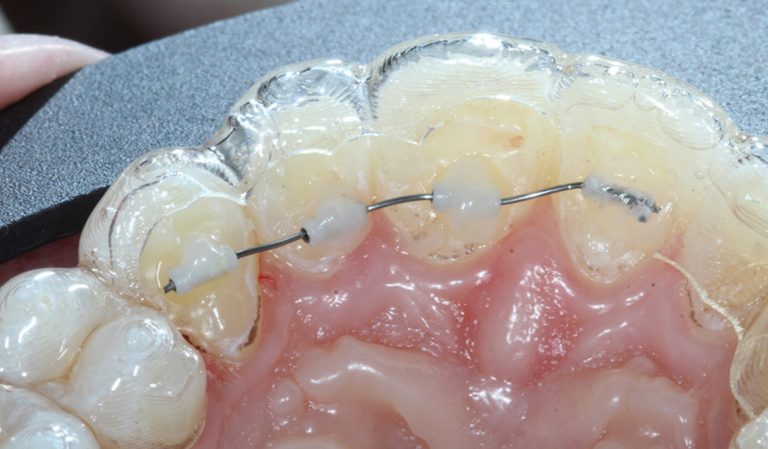

Biomecánica de extracciones de premolares con alineadores: reporte de caso y revisión de literatura

El artículo que compartimos el día de hoy se llama Biomechanically Valid Clear Aligner Therapy for Premolar Extraction … [Leer más...] acerca de Biomecánica de extracciones de premolares con alineadores: reporte de caso y revisión de literatura